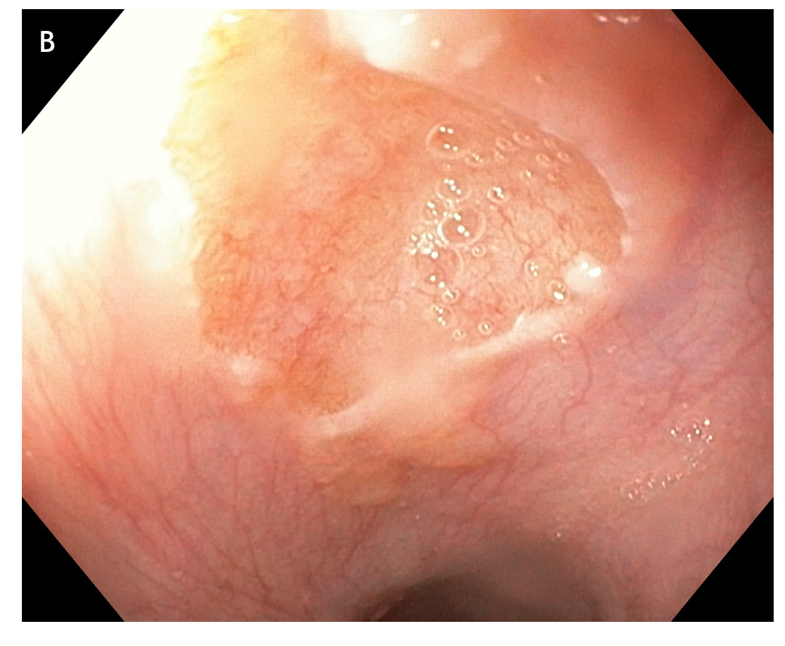

Other issues such as elevated surfaces[78] or the size of the IP should be taken into consideration before deciding which strategy is most appropriate. For instance, experts generally did not include patients with large IPs in the previously conducted interventional APC trials to exclude the possibility of stricture formation[18,79–81]. Furthermore, large areas of resected tissue and multiple lesions were independent predictors of stricture formation[82] (Figure 5).

Figure 5 large areas of resected tissue and multiple lesions were independent predictors of stricture formation. A: Three areas of cervical inlet patches, with kissing distribution, in a middle age women with uterine cancer history, presenting for reflux complaints and globus sensation. Detailed image in (B) white light endoscopy and (C) narrow band imaging. D: Irregular Z line in the same patient suggesting concomitant gastroesophageal reflux disease.